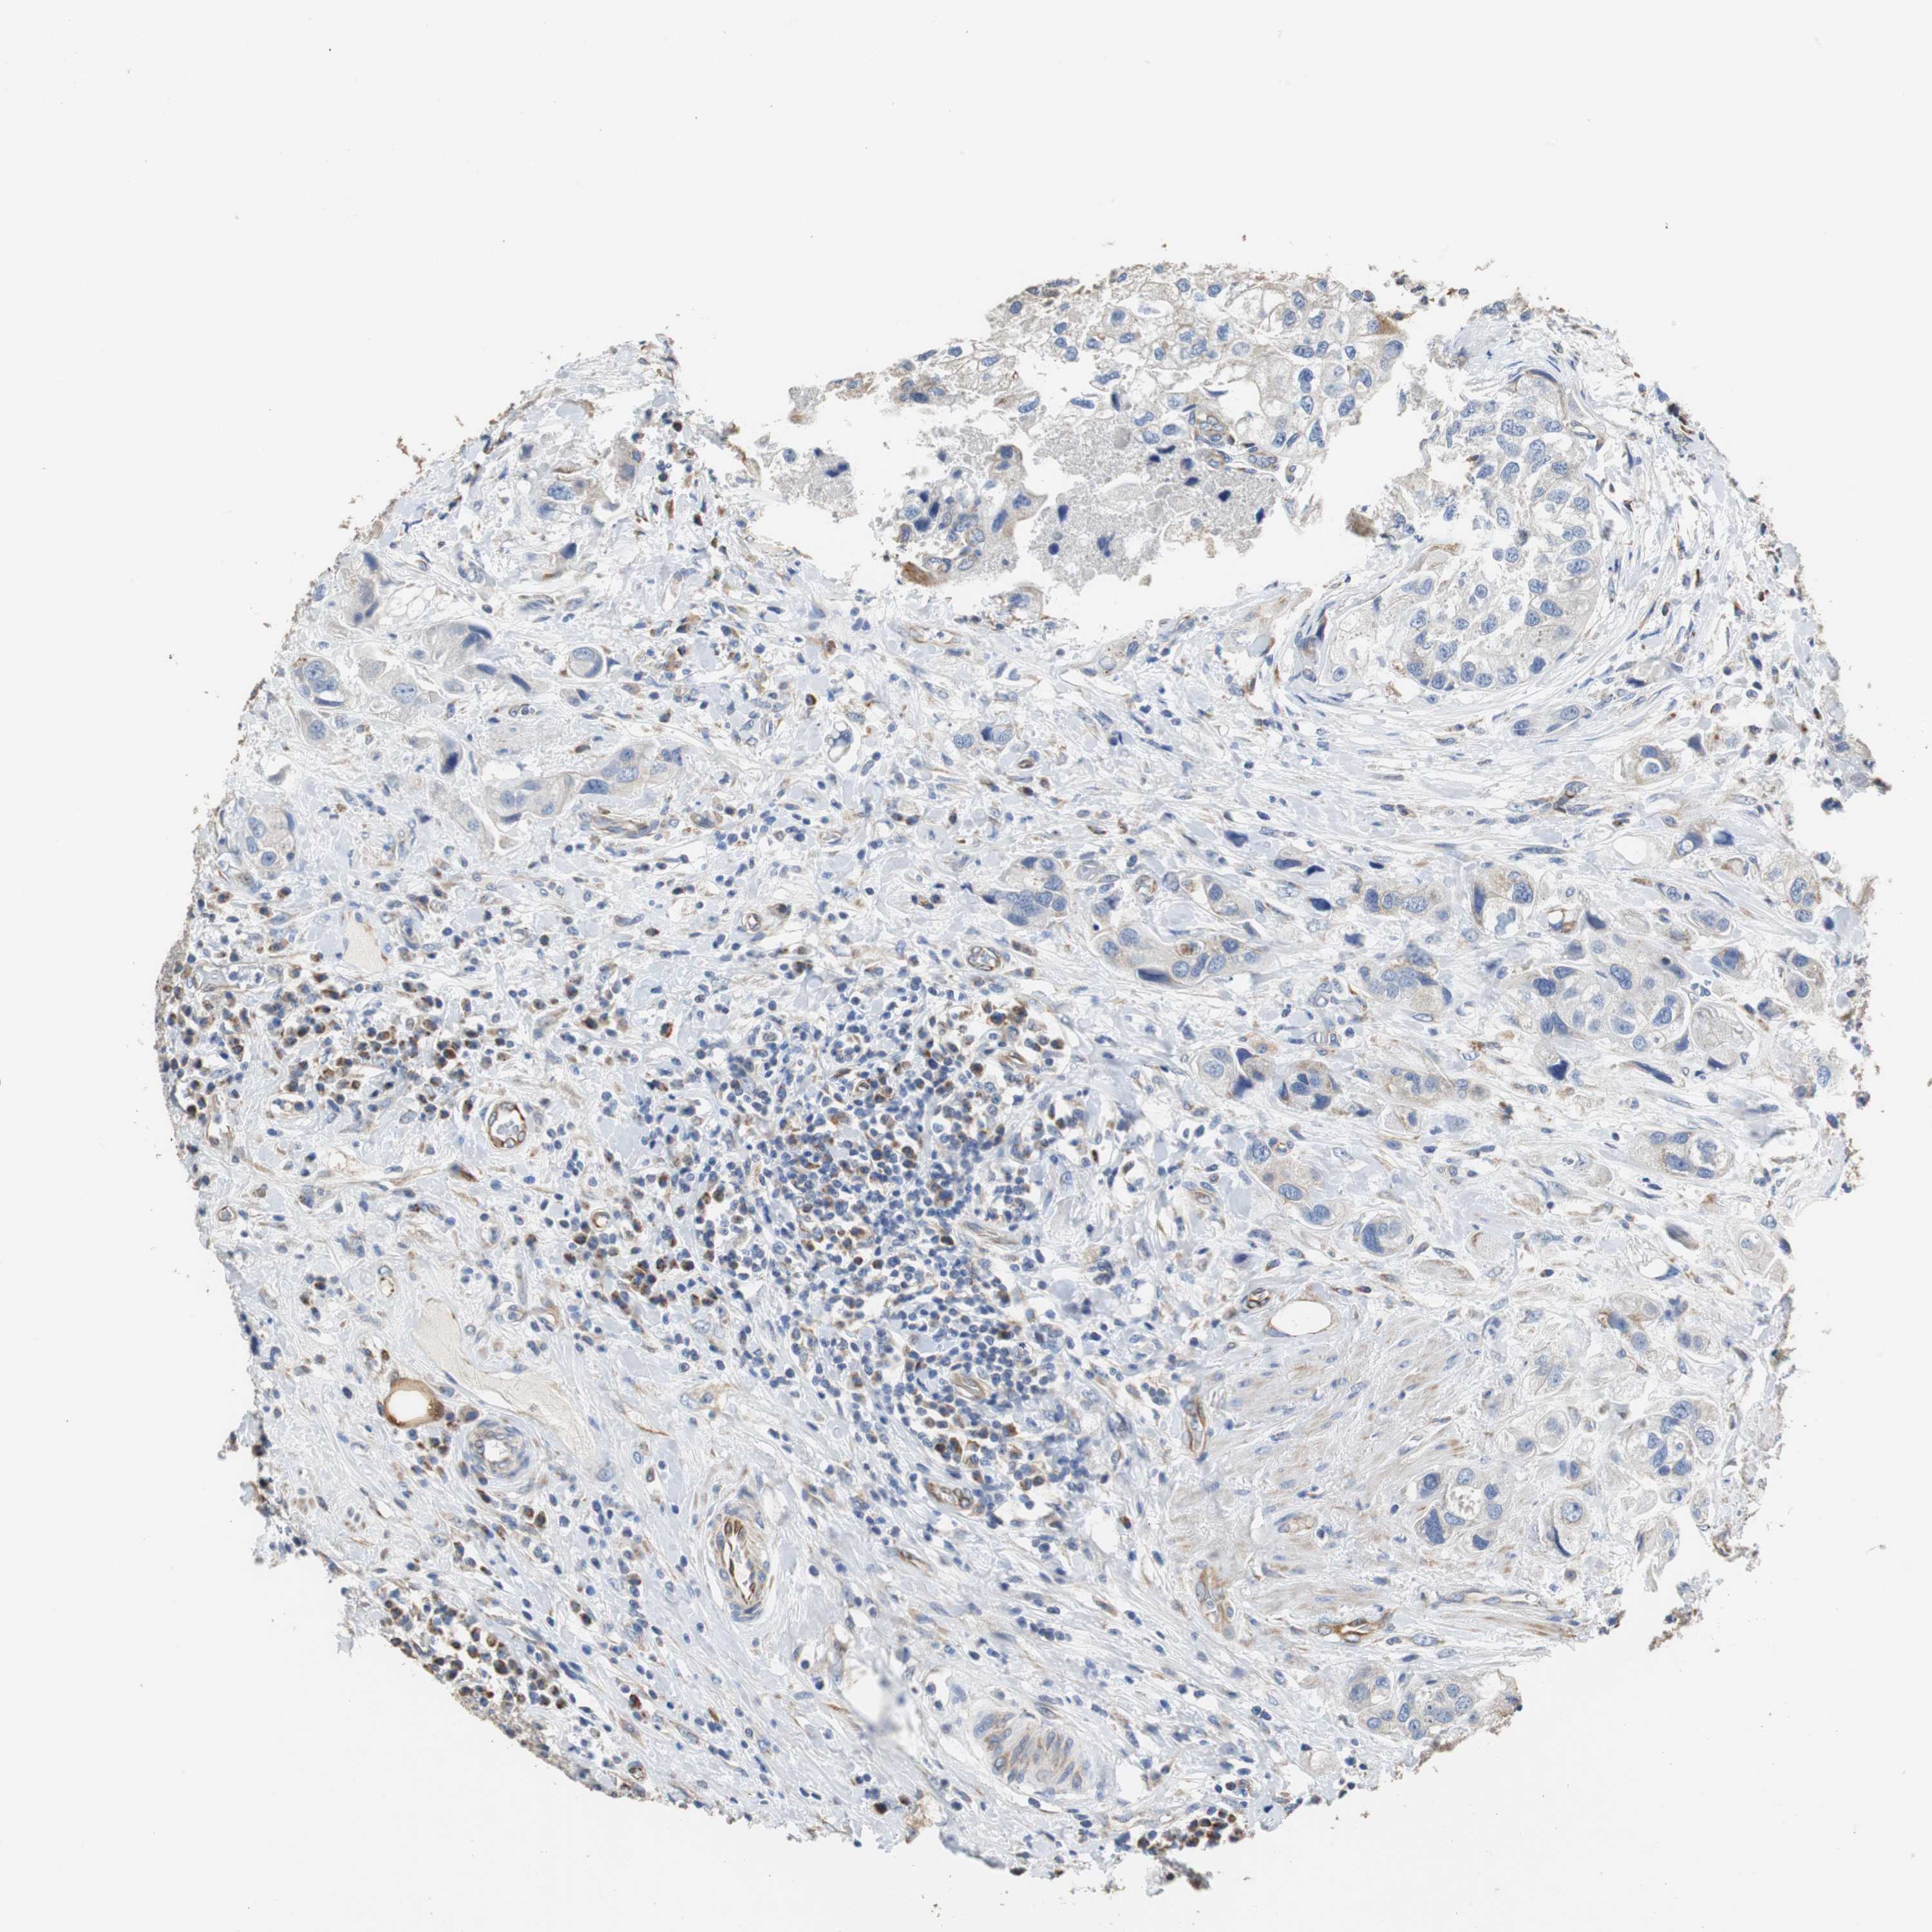

UROTHELIAL CANCER - Protein expressioni

A mouse-over function shows sample information and annotation data. Click on an image to view it in a full screen mode. Samples can be filtered based on level of antibody staining by selecting one or several of the following categories: high, medium, low and not detected. The assay and annotation is described here.

Note that samples used for immunohistochemistry by the Human Protein Atlas do not correspond to samples in the TCGA dataset.

Antibody stainingi

Antibody staining in the annotated cell types in the current human tissue is reported as not detected, low, medium, or high, based on conventional immunohistochemistry profiling in selected tissues. This score is based on the combination of the staining intensity and fraction of stained cells.

Each image is clickable and will lead to virtual microscopy that enables deeper exploration of all samples and also displays staining intensity scores, fraction scores and subcellular localization as well as patient and tissue information for each sample.

Antibody HPA006277

Antibody HPA006507

Antibody CAB017027

Staining

High

Medium

Low

Not detected

Intensity

Strong

Moderate

Weak

Negative

Quantity

>75%

75%-25%

<25%

None

Location

Nuclear

Cytoplasmic/membranous

Cytoplasmic/membranous,nuclear

Urothelial carcinoma, Low grade

Urothelial carcinoma, High grade